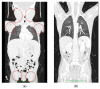

Simultaneous multilineage hematologic malignancies are uncommon and associated with poorer prognosis than single-lineage leukemia or lymphoma. Here, we describe a concomitant malignant neoplasm in a 4-year-old boy. The child presented with massive lymphoproliferative syndrome, nasal breathing difficulties, and snoring. Morphological, immunocytochemical, and flow cytometry diagnostics showed coexistence of acute myeloid leukemia (AML) and peripheral T-cell lymphoma (PTCL). Molecular examination revealed a rare t(9;9)(q34;q34)/SET::NUP214 translocation as well as common TCR clonal rearrangements in both the bone marrow and lymph nodes. The disease showed primary refractoriness to both lymphoid and myeloid high-dose chemotherapy as well as combined targeted therapy (trametinib + ruxolitinib). Hence, HSCT was performed, and the patient has since been in complete remission for over a year. This observation highlights the importance of molecular techniques for determining the united nature of complex SET::NUP214-positive malignant neoplasms arising from precursor cells with high lineage plasticity.